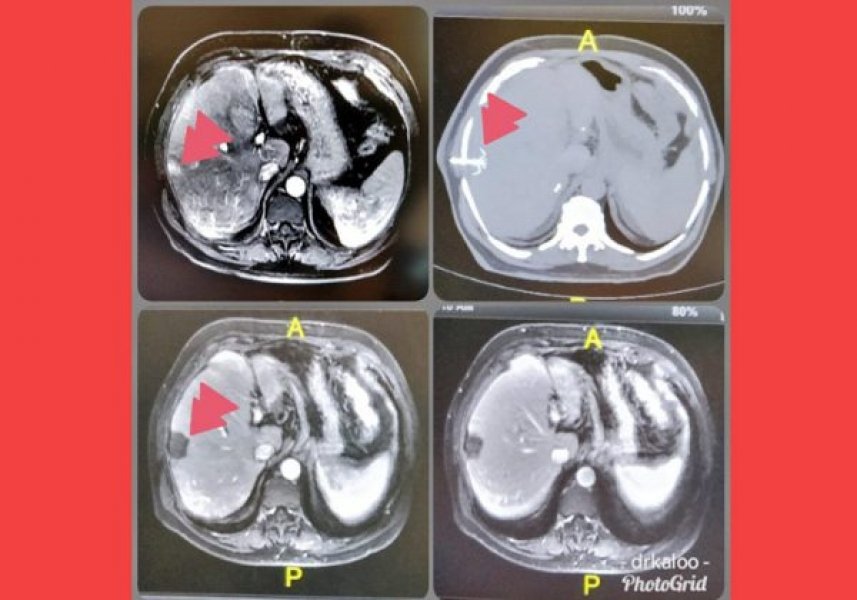

Na ablação, o médico utiliza uma agulha que é inserida no órgão afetado, até a ponta encontrar o tumor.

Para localizá-lo, são usadas imagens de ultrassom ou de tomografia.